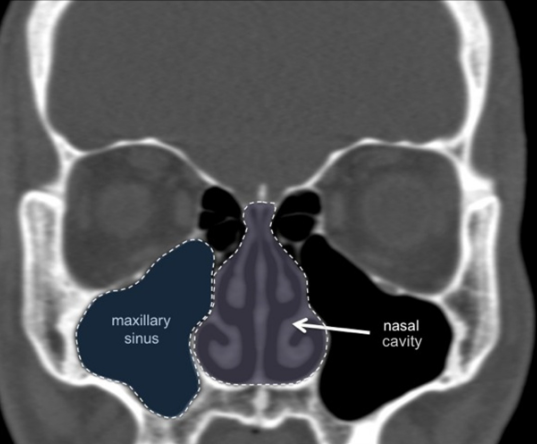

- Maxillary sinus evaluation:

- Assessment of sinus floor morphology

- Maintenance of at least 1mm clearance unless performing a sinus lift

- Consideration of septa and other anatomical variations